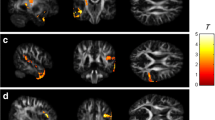

Voxel-wise modified TBSS analysis

Table 4 shows the results of the whole brain voxel-wise analysis. The pairwise group differences show a significant decrease in FA in the BC + SYST group vs. the NC group in a large number of voxels. Figure 4 shows a widespread bilateral distribution of affected white matter regions with a posterior dominance. Involved tracts include bilateral superior longitudinal fasciculus (SLF), bilateral sagittal stratum, bilateral posterior thalamic radiation, bilateral cingulum, bilateral corticospinal tract, bilateral corona radiata, splenium and body of the corpus callosum. For the BC-SYST vs. NC contrast, we also found a decrease in FA, albeit in a much lower number of voxels. Affected regions included left SLF, left corticospinal tract, left corona radiata, splenium of corpus callosum. At our predetermined threshold of p < .05 (TFCE, FWE corrected) we did not find significant group differences in decline in FA between BC + SYST and BC-SYST. When inspecting the results at a p < .001 uncorrected, however, we observed some small foci including bilateral SLF, indicating a steeper decrease of FA in these regions in the BC + SYST than the BC-SYST group. Few significant differences were found with regard to MD. The BC + SYST vs. NC comparison showed a significant decrease in MD in BC + SYST relative to NC in the body of the corpus callosum. When directly comparing BC + SYST vs. BC-SYST at an uncorrected p < .001 we found a steeper decrease in MD for BC + SYST than BC-SYST in the left sagittal stratum and left retrolenticular part of the internal capsule.

Results from voxel-wise modified TBSS analysis of FA maps. Effects show a decrease in FA from M1 to M2. BC + SYST < NC: more decrease in patients exposed to chemotherapy ± endocrine treatment vs. no cancer controls; BC-SYST < NC: more decrease in cancer patients not exposed to systemic treatment vs. no cancer controls; BC + SYST < BC-SYST: more decrease in patients exposed to chemotherapy ± endocrine treatment vs. cancer patients not exposed to systemic treatment. Analyses are TFCE corrected at p < .05 except for the BC + SYST < BC-SYST contrast. Significant effects are overlaid on the average FA of all participants. Statistical analyses were performed in native space. For visualization and anatomical reference, results were warped to MNI space

Moreover, our voxel-wise analysis showed a widespread reduction in FA from baseline to 6 months after chemotherapy when compared to the NC group (women without a cancer diagnosis). Affected white matter regions were largely bilaterally and somewhat posteriorly localized, including SLF, posterior thalamic radiation, cingulum, corticospinal tract, corona radiata and the splenium and body of the corpus callosum. These regions overlap with those previously reported in the longitudinal study by Deprez and coworkers (Deprez et al. 2012) who also did not skeletonize their data and used in-house developed registration algorithms to warp individual FA maps to a study-specific FA template (T1 scans were not used). A follow-up study to Deprez et al. (Billiet et al. 2018) observed a return to baseline values of FA 3 to 4 years after chemotherapy, suggesting recovery of white matter integrity after initial injury. Application of a skeletonization step might also explain the absence of voxel-based decline in FA in other studies in the field of CRCI (Chen et al. 2019; Correa et al. 2016; Mo et al. 2017).